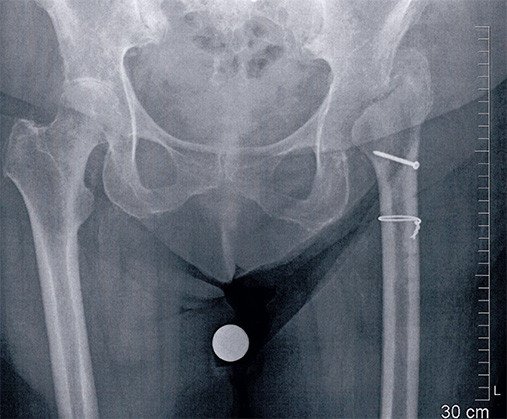

Die weiteren Abklärungen zeigten, dass die Hüftmuskulatur teilweise abgerissen war. Die Hüfte wurde revidiert. Der Teilabriss des Hüftmuskels (Musculus glutaeus medius) konnte intraoperativ bestätigt werden. Deshalb wurde die Hüftprothese wieder ausgebaut. Der Ausbau eines zementfreien Schaftes macht zumeist die Längsspaltung des Oberschenkelknochens nötig. Der Muskel wird mit starken Fäden gefasst, die durch den Oberschenkelknochen gezogen werden. Die Nähte werden zusätzlich über eine Schraube gesichert. Meistens wird auch die Hüftpfanne entfernt. Zum einen kommt es sonst zu einem schmerzhaften Reiben zwischen dem Oberschenkelknochen und der Pfanne und zum andern wird die Pfanne meist sicherheitshalber entfernt, um eine evtl. vorhandene Infektion antibiotisch wirkungsvoll behandeln zu können (mit einem zurückgelassenen Implantat ist eine antibiotische Behandlung meistens schwierig).

Die Hüfte wird dann 8 Wochen in diesem Zustand belassen. Während dieser Zeit kann ein Patient, je nach Alter, einige Schritte gehen oder ist manchmal auch auf einen Rollstuhl angewiesen. Falls er im Rollstuhl nach Hause kann, wird dies nach ca. 2 Wochen der Fall sein. Ansonsten bemüht sich unser Case Management, einen Platz zu finden bis eine gewisse Selbstständigkeit erreicht ist oder bis zum Wiedereinbau.